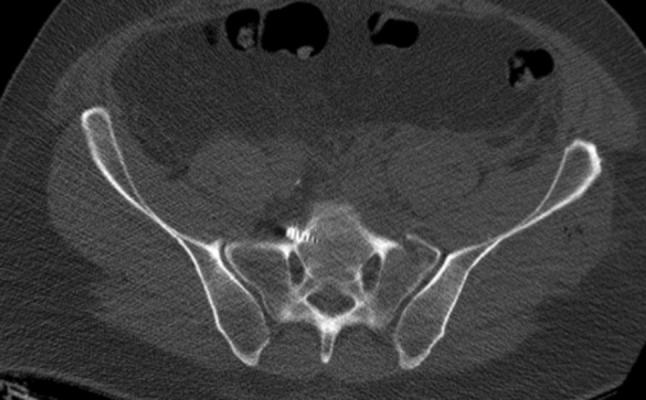

Fig. 1.

Anterior penetration of contralateral anterior sacral wall with L5-root palsy